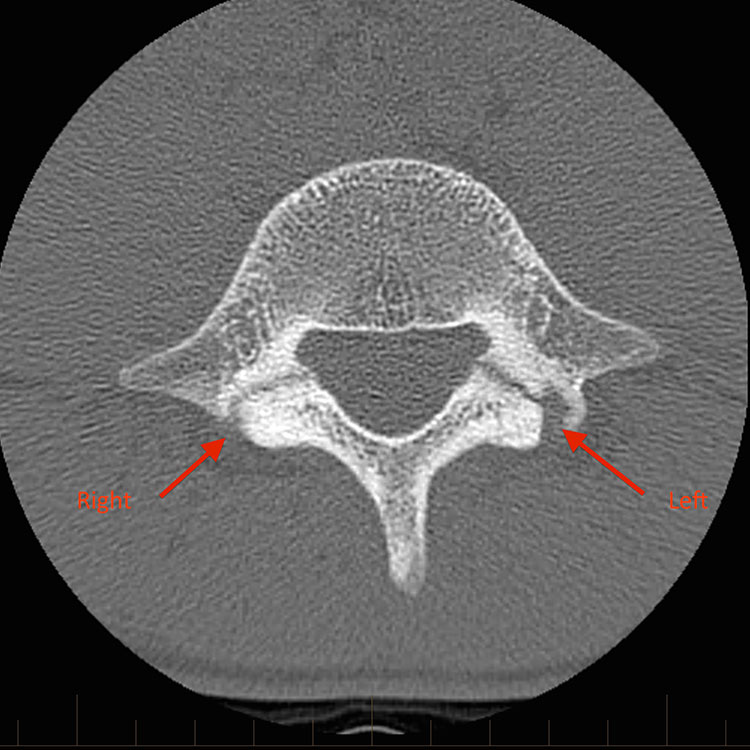

ΑΞΟΝΙΚΗ

Αυτή η μέθοδος μπορεί να απαιτείται για την απεικόνιση καταγμάτων του φλοιού στα οστά που δεν οραματίζονται εύκολα με ακτινογραφίες. Αυτά τα οστά περιλαμβάνουν το σκαφοειδές και το ισθμό των σπονδύλων. Η αξονική τομογραφία πρέπει να χρησιμοποιείται με σύνεση, ιδιαίτερα στα παιδιά, λόγω του αυξημένου κινδύνου καρκίνου από τη δόση ακτινοβολίας.

ΣΠΟΝΔΥΛΟΛΥΣΗ

Τα κατάγματα λόγω πίεσης του ισθμου σπονδύλου (σπονδυλόλυση) είναι μια σχετικά συχνή αιτία επίμονου πόνου στη μέση στον νεότερο ποδοσφαιριστή.20 Η περιοχή pars είναι εκείνη η περιοχή του ελάσματος που βρίσκεται κάτω από την κάτω αρθρική απόφυση του σπονδύλου πάνω. Το ίδιο το έλασμα είναι η λεπτή γέφυρα οστού που συνδέει το μίσχο με την ακανθώδη απόφυση. Η σπονδυλολίσθηση είναι η πρόσθια ολίσθηση ενός σπονδυλικού σώματος σε σχέση με τον γειτονικό του σπόνδυλο και αυτό αναπτύσσεται σε περίπου 5% των αθλητών με κατάγματα πίεσης παρ. Είναι συχνότερο σε νεότερες, σκελετικά ανώριμες αθλήτριες και γυναίκες.21

Διερευνήσεις

Οι ακτινογραφίες μπορούν να ανιχνεύσουν χρόνια, πλήρη κατάγματα από το στρες, αλλά δεν θα ανιχνεύσουν οξέα κατάγματα από το στρες. Η μαγνητική τομογραφία είναι γενικά η μέθοδος εκλογής. Οίδημα μυελού των οστών μπορεί να φανεί στην περιοχή pars και μια γραμμή κατάγματος μπορεί να είναι ορατή στην σταθμισμένη εικόνα T1. Μπορεί να απαιτείται στοχευμένη αξονική τομογραφία για τον περαιτέρω χαρακτηρισμό της παρουσίας και της πληρότητας μιας γραμμής κατάγματος. Δεδομένου ότι το οίδημα μυελού των οστών στη μαγνητική τομογραφία μπορεί να διαρκέσει πολύ πέρα από το στάδιο της κλινικής επούλωσης, η σειριακή μαγνητική τομογραφία δεν χρησιμοποιείται για την παρακολούθηση συμπτωματικών ασθενών.

Μερικές εικόνες που δείχνουν τραυματισμούς που αφορούν τον ισθμό των σπονδύλων.